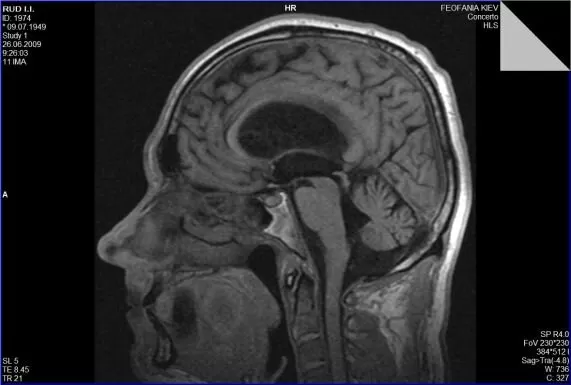

Гідроцефалія, або водянка головного мозку, — це патологічний стан, який характеризується накопиченням цереброспінальної рідини (ліквору) у шлуночках мозку та міжоболонкових просторах.

Звернутися з метою обстеження та верифікації діагнозу гідроцефалії із наступним нейрохірургічним втручанням ви можете Центрі Нейрохірургії «Оберіг». До переліку обстежень входить стандартний лабораторний пакет загальноклінічних аналізів та МРТ головного мозку.